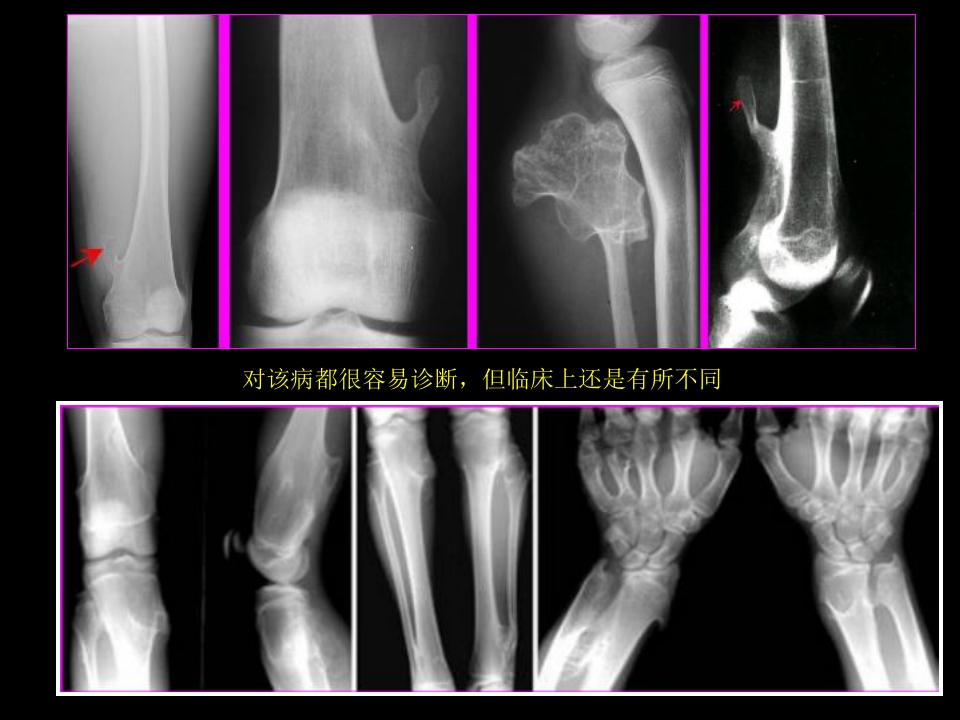

骨肿瘤影像学诊断